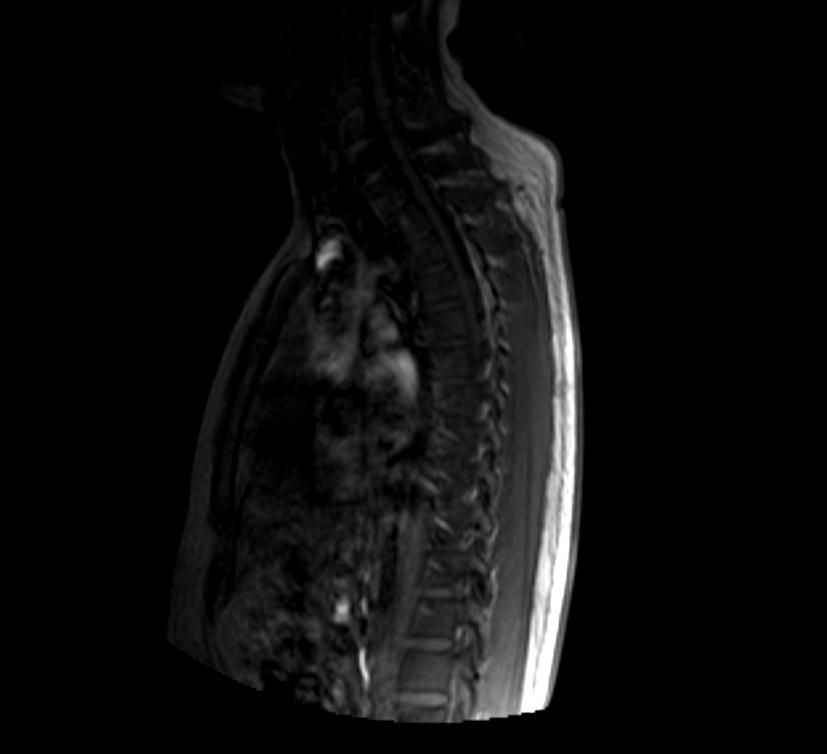

• 우선 이 영상은 T2 강조 시상면(sagittal) MRI 영상으로 보이며, 전체 척추를 한 번에 촬영한 전척추(whole spine) 스크리닝 영상으로 판단됩니다.

말씀하신 "상체 부분 중간의 하얀 음영"은 흉추(thoracic spine) 부위에서 보이는 T2 고신호(high signal intensity) 병변으로 보입니다. T2 영상에서 밝게 보인다는 것은 해당 부위에 수분 함량이 높은 조직이 있다는 의미인데, 이것이 곧 악성 병변을 의미하지는 않습니다.

가능한 감별 진단을 말씀드리면, 우선 가장 흔한 원인은 추간판(intervertebral disc) 내의 수분 변화 혹은 Schmorl's node처럼 양성 구조적 변화입니다. 그 외에 혈관종(vertebral hemangioma)은 척추에서 매우 흔하게 발견되는 양성 종양으로, T2에서 밝게 보이는 전형적인 소견을 보입니다. 척추 혈관종은 성인의 10퍼센트 이상에서 우연히 발견될 만큼 흔하며 대부분 치료가 필요 없습니다.

물론 영상 한 장만으로 확정적인 판독은 어렵고, 전체 시퀀스(T1, T2, 조영증강 여부 등)와 임상 증상을 함께 고려해야 정확한 판단이 가능합니다.